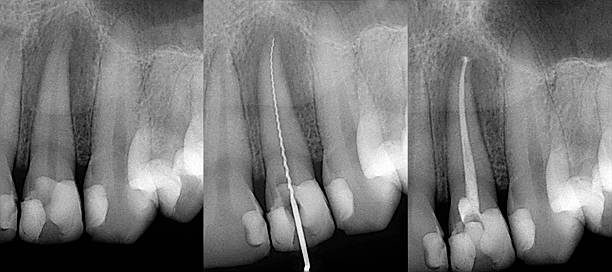

신경치료(근관치료)는 치아 내부의 감염된 신경과 혈관 조직을 제거하고, 내부를 소독·충전하여 치아를 살리는 치료입니다.

신경치료는 대부분 2~3회 이상 나누어 진행됩니다.